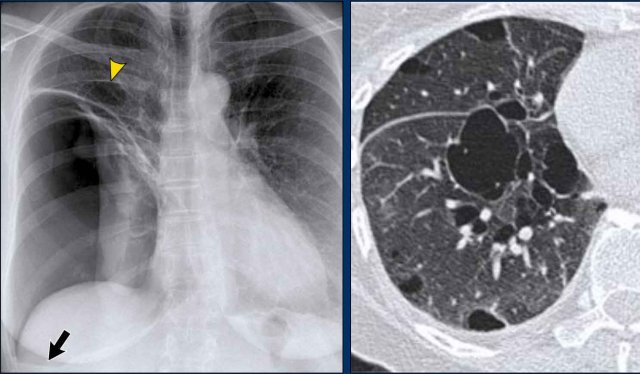

Vena azygos lobe, seen as a fine line that crosses the apex of the right lung. Vena azygos lobe, seen as a fine line that crosses the apex of the right lung.

Vena azygos lobe

A common normal variant, the azygos lobe, is formed when the azygos vein takes an anomalous lateral course, creating a deep pleural fissure in the upper lobe of the right lung.

On radiographs, it appears as a thin curvilinear line traversing the right upper lung field, frequently ending in a teardrop-shaped density (the azygos vein) within the azygos fissure.

Here another patient with an azygos lobe.

The azygos vein is seen as a thick structure within the azygos fissure.

Another anatomical variant involves an accessory articulation at the anterior first rib (arrow).

At the junction of the bony and calcified cartilaginous segments, a pseudoarticulation may simulate a pulmonary nodule or mass on frontal imaging.